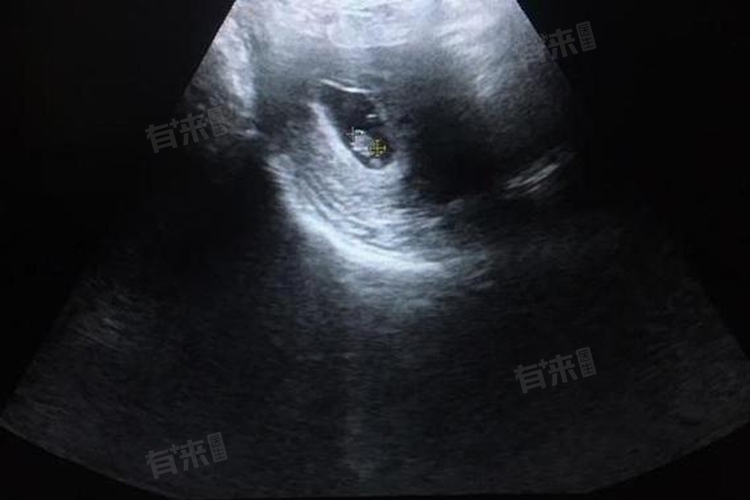

当孕妇怀孕8周时,B超检查发现有孕囊但无胎心和胎芽,这可能意味着胚胎发育异常,包括受孕时间短、黄体功能不全、胚胎染色体异常等,根据不同原因给予对应的措施,如均衡营养、药物治疗等。